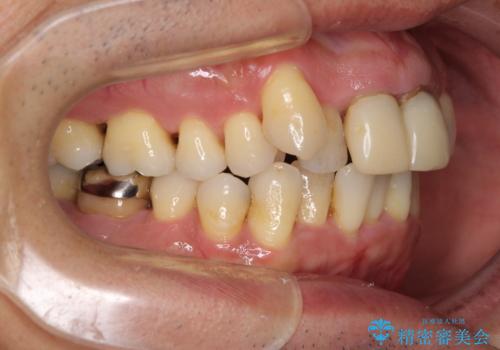

- 八重歯を気にして来院された患者様です。

上顎前歯の突出感と右上の八重歯を気にされていたので、上顎左右の第一小臼歯2本を抜歯し、ワイヤー装置にて矯正治療を行うこととしました。

食いしばりにより奥歯がすり減っており、咬み合わせが定まるまで時間がかかりましたが、整った口もに仕上がりました。